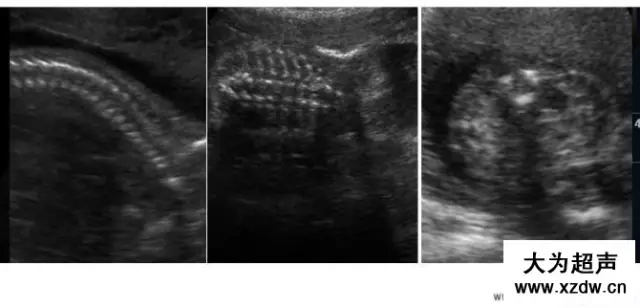

產(chǎn)科超聲正常圖片